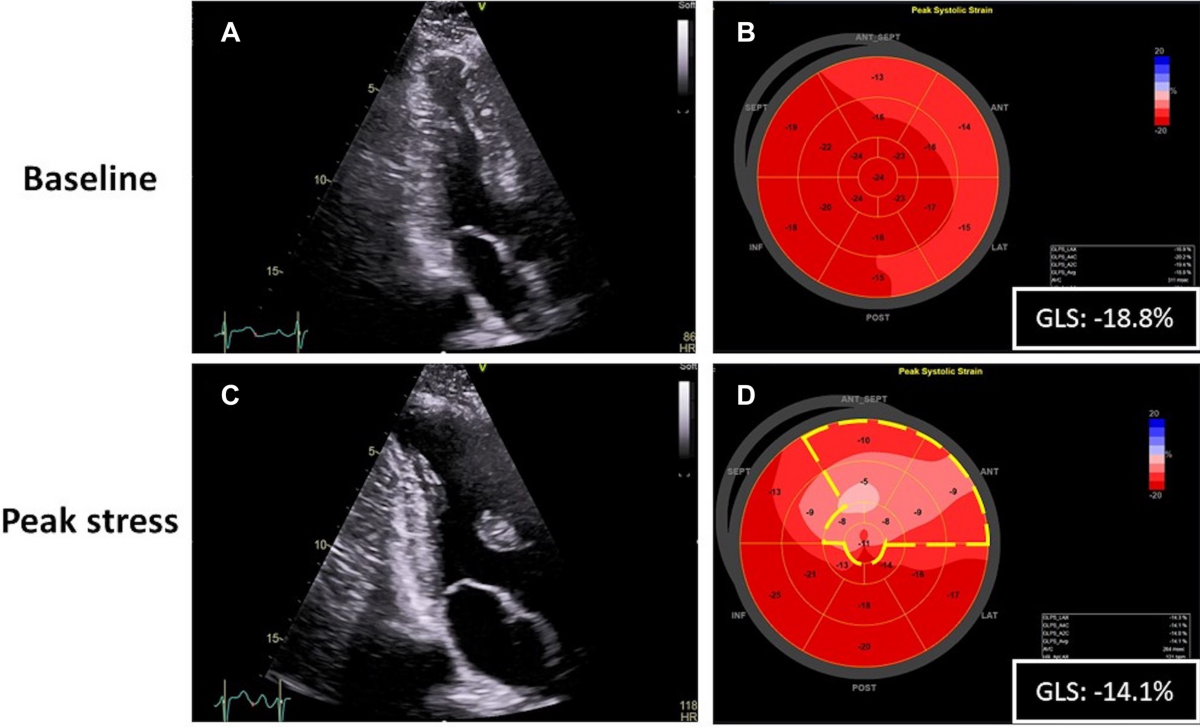

» Interpreting strain echo (98) 사진

Interpreting strain echo (98) 사진